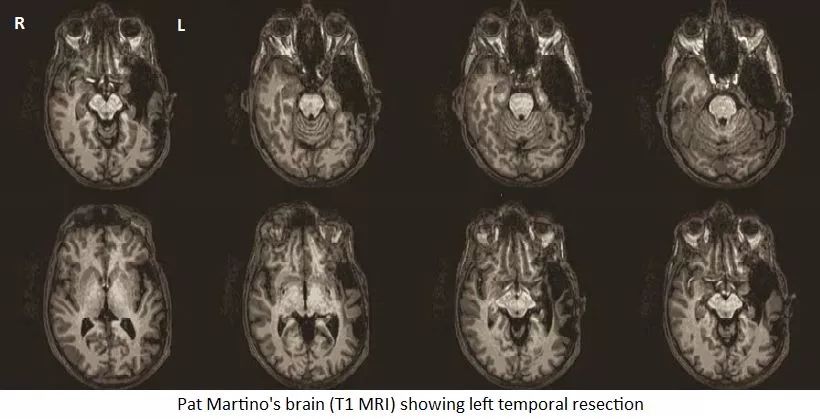

可以清晰地看到术后马蒂诺左颞叶的大部分已经被切除。图源:discovermagazine

手术分为两个阶段:第一步,医生移除已经形成的血块。然后,他们实施脑部血管造影术,使染色剂进入大脑流动的血液中,在 X 光照射的照射下,医生就能看到哪一部分大脑必须切除。为了移除“那一团虫子”,西蒙尼医生切除了马蒂诺左颞叶的 70% 。